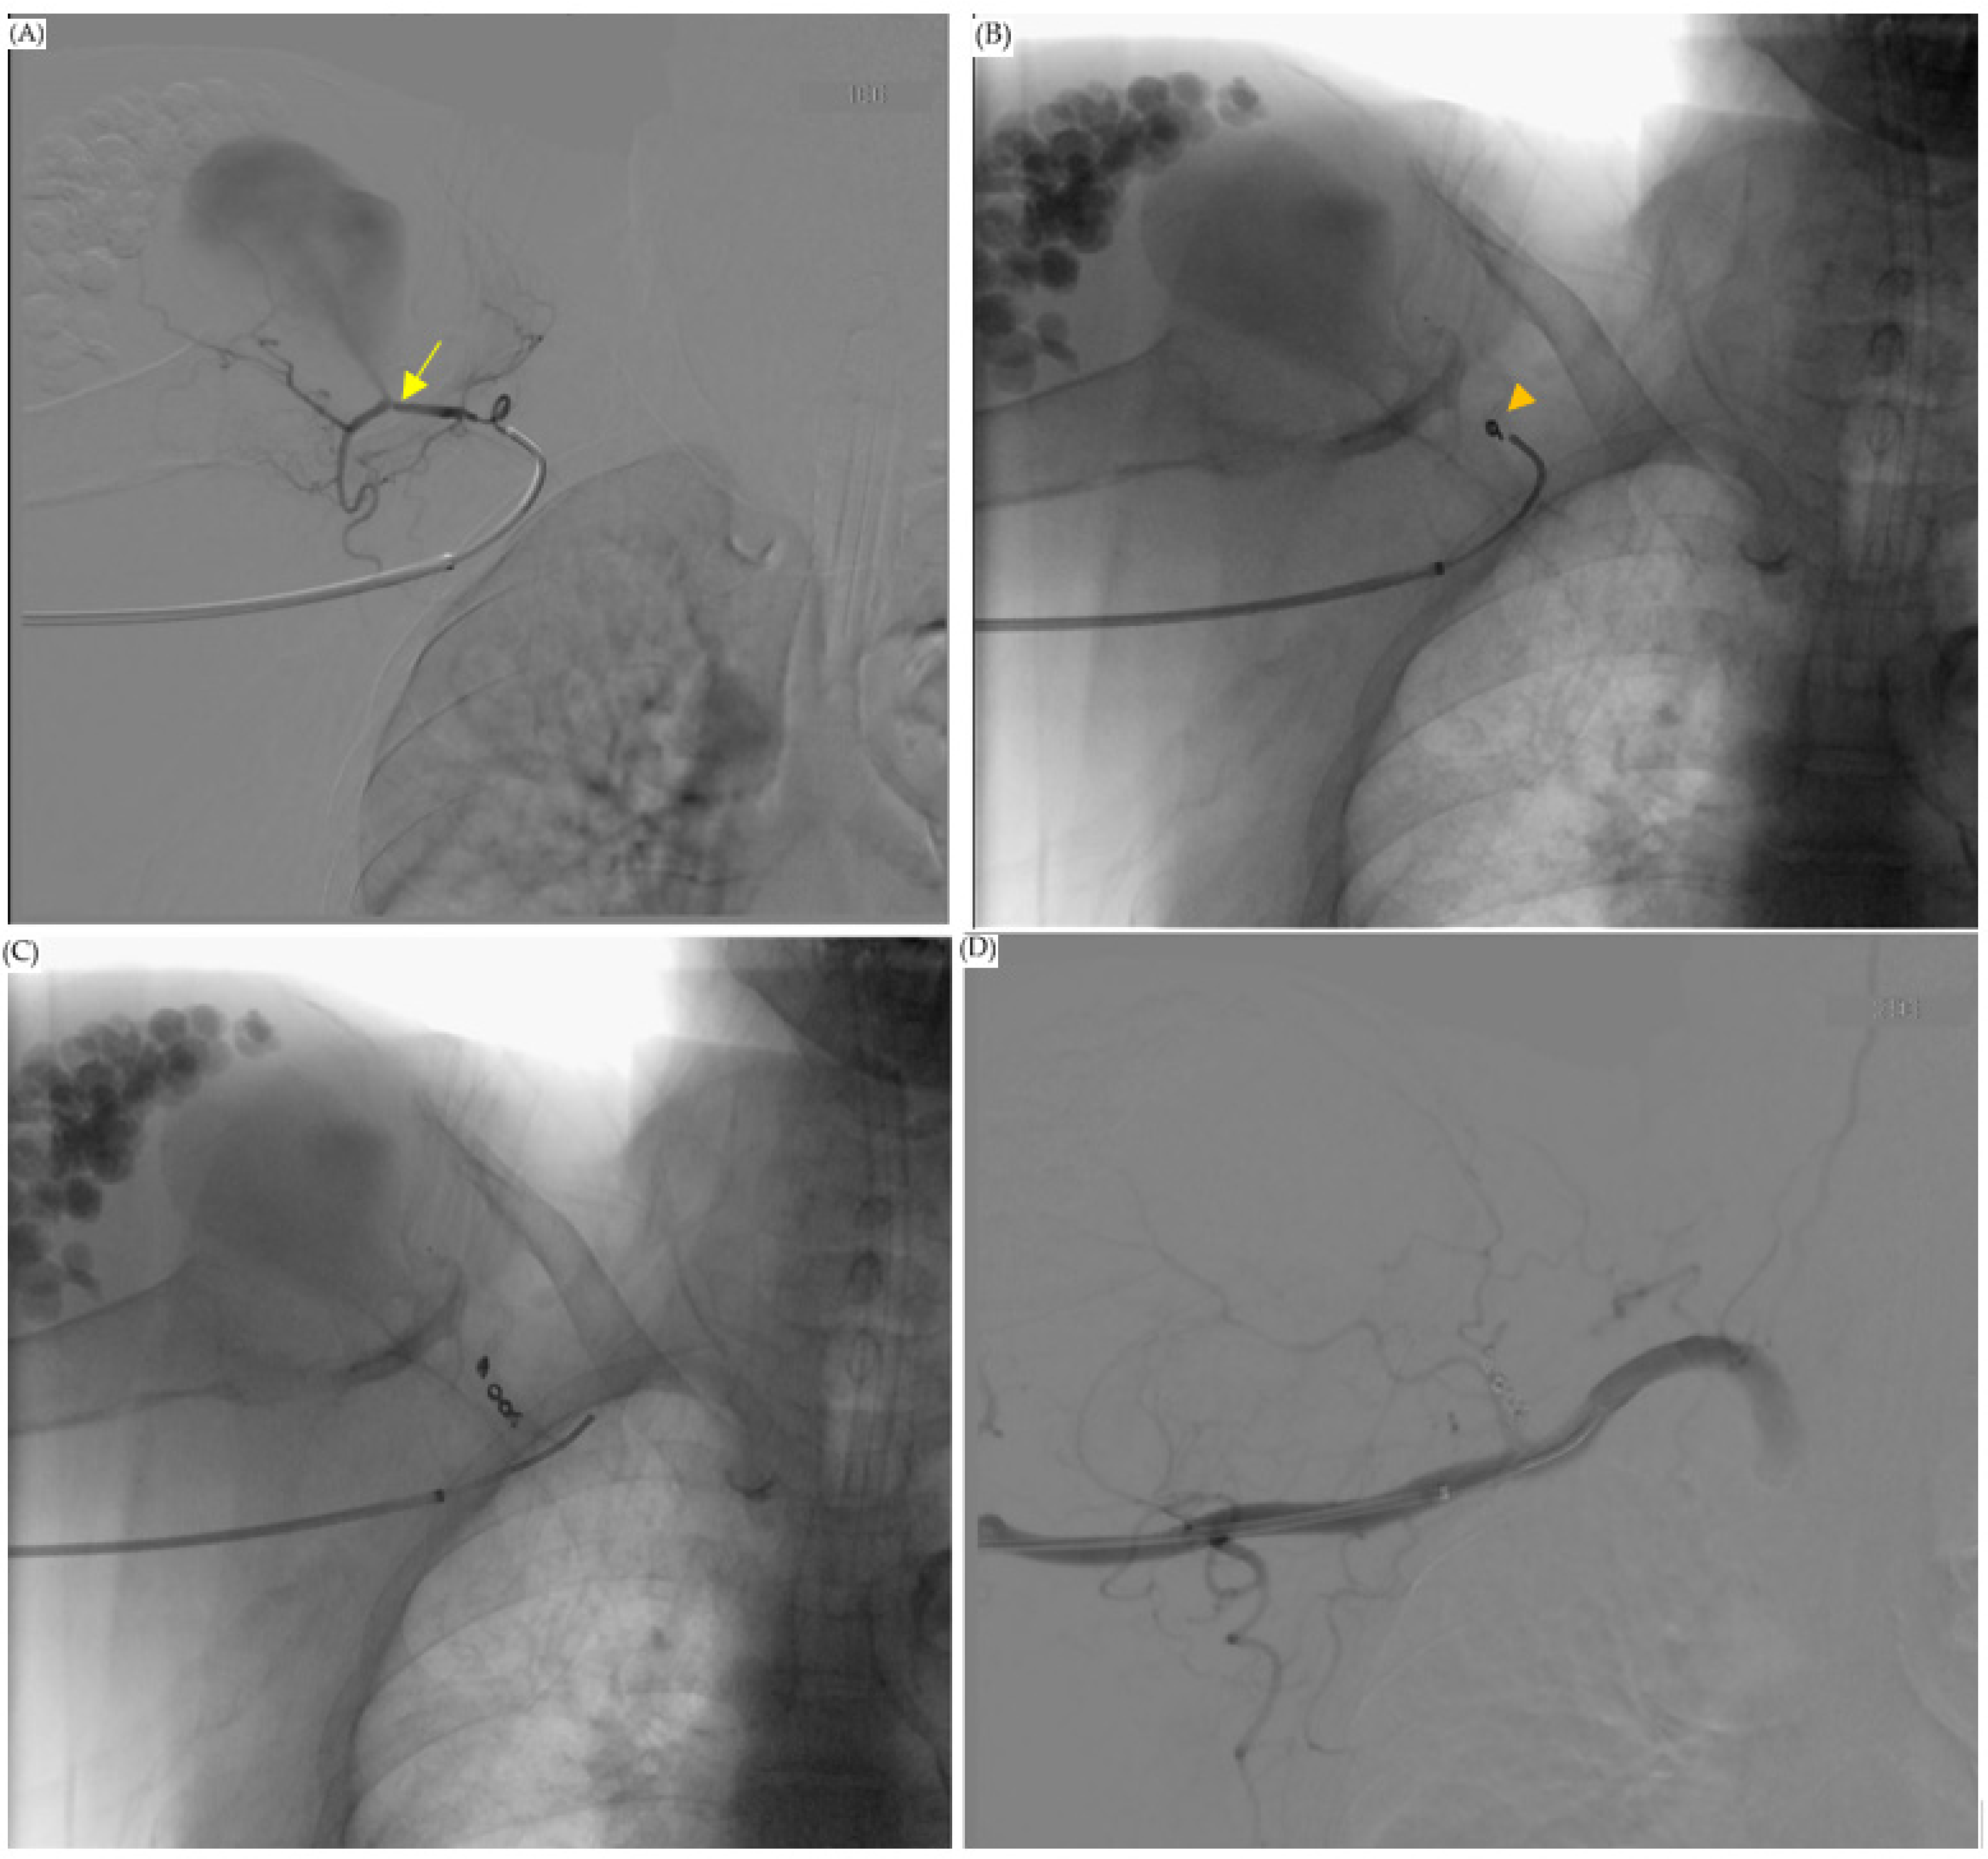

Figure 2.

CT-guided drainage of the abscess. (A,B) were the first CT-guided pigtail drainage; (C,D) were the second CT-guided pigtail drainage; the abscess of the subdeltoid space was mildly decreased. However, local swelling only mildly decreased.